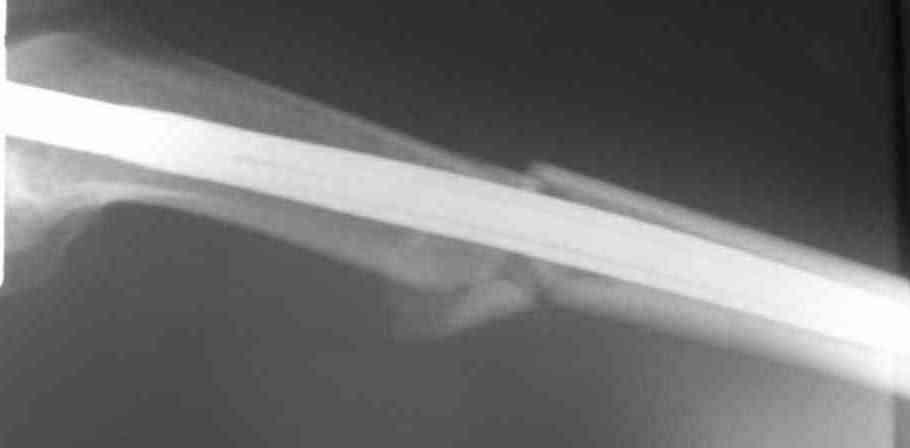

Дорогой Александр. Имею скромный опыт использования системы Fixion при переломах плеча, бедра и тибии. Всего 18 наблюдений с сентября 2006 г. Результаты отличные. Гвоздь индивидуален для каждого медуллярного канала. Легко имплантируется как в узкий, так и в деформированный канал. Это позволяет применять метод интрамедулярного остеосинтеза без ненужных потерь времени операции, флюороскопии и реально снижает крвопотерю и операционный риск. Удаление происходит без проблем. Особенно интересны больные с ипсилатеральными переломами бедра и голени.

В отношении ранней нагрузки при спиральных переломах лучше не торопиться. По данному случаю необходимо достигнуть исчезновения щели между штифтом и внутреним кортексом по Rg. А так картинка прекрасная - и длина сегмента и репозиция. Можно поздравить, коллега!